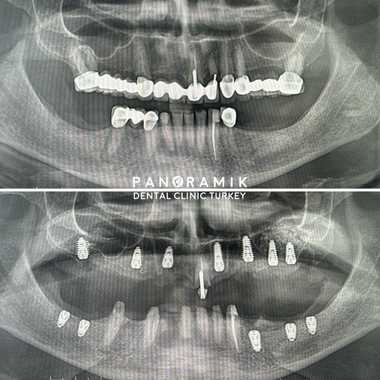

This is a dental operation performed to increase the volume of bone tissue in the upper jaw. During implant treatment in case of insufficient bone tissue in the area of the upper molars and premolars, patients need to have an operation called sinus lifting. There are two types of sinus lifting methods: open and closed.

Open (lateral) sinus lifting: It is a mini-surgical operation performed with local anesthesia in cases where the bone height is below 4 millimeters.

Closed (internal) sinus lifting: It is applied in cases where the bone height is between 4mm-7mm. The floor of the sinus is raised using a special instrument called an osteotome and filled with bone graft. This procedure is performed using local anesthesia. Sinus lifting operations are painless procedures that take 30-60 minutes. İf there is enough bone tissue, implants can be installed in the same session.